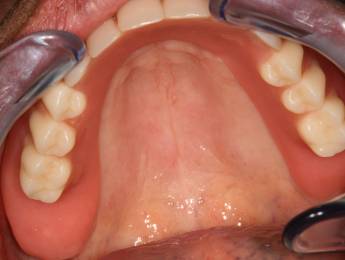

3. eset

4 implantátumra rögzített stéggel stabilizált "Overdenture" megoldás. Költséghatékony módszer fogsorok rögzítésére. Nagyfokú stabilitás érhető el redukált felületeken. Ebben az esetben jól látható, hogy a szájpadlást nem fedi be a kivehető fogsor, az ízlelés is megmarad, mégis javul a rágási képesség és a fogsorok mozgásmentesen rögzülnek.